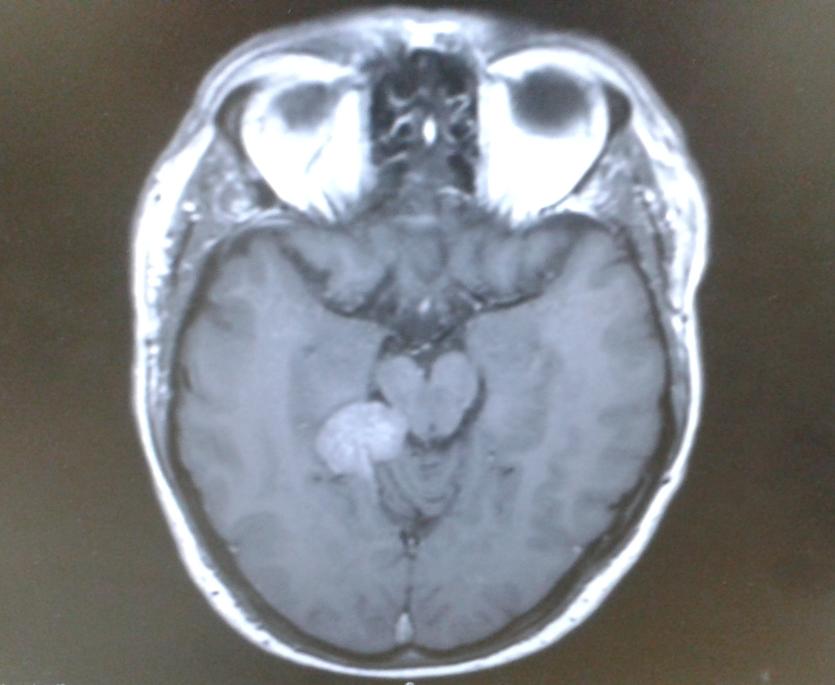

Darren was diagnosed in July 2015 with an inoperable tentorial meningioma, a slow-growing, low-grade tumour at the base of his brain. He underwent gamma knife radiosurgery at the Northern General Hospital in Sheffield, a highly targeted form of radiotherapy that uses over 300 beams of radiation to destroy tumour cells while sparing healthy tissue.